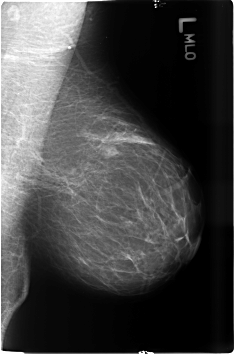

B_3482_1.LEFT_MLO

LEFT_MLO LINES 4600 PIXELS_PER_LINE 3040 BITS_PER_PIXEL 12 RESOLUTION 50 NON_OVERLAY